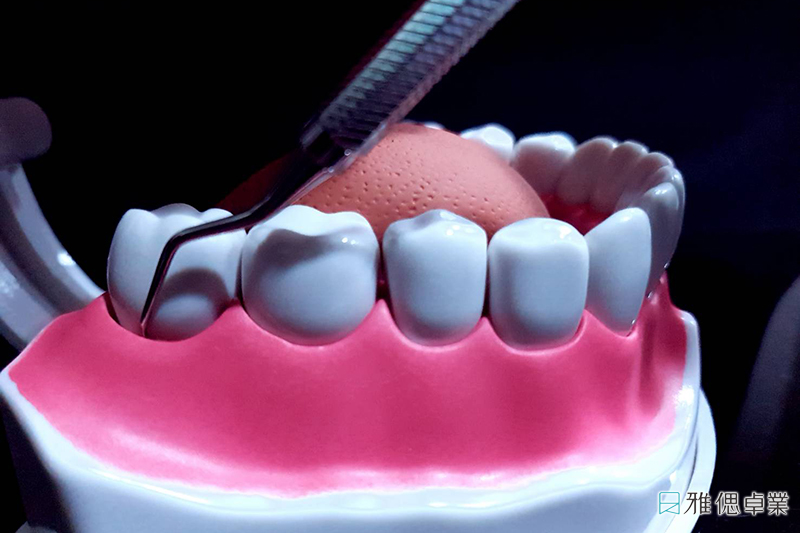

顯微微創牙周病輔助治療,高精密的治療處理

在牙周病的治療過程中,專業牙醫師利用高倍數顯微鏡儀器放大牙周各處發炎病灶,以微創方式將高精密治療器械深入牙周囊袋底部,徹底刮除牙周囊袋內的牙結石、完整清除牙根表面的毒素,抑制細菌發炎,使恢復期中的牙周病傷口更容易穩定癒合,提供患者專業精準的牙周病治療處理。